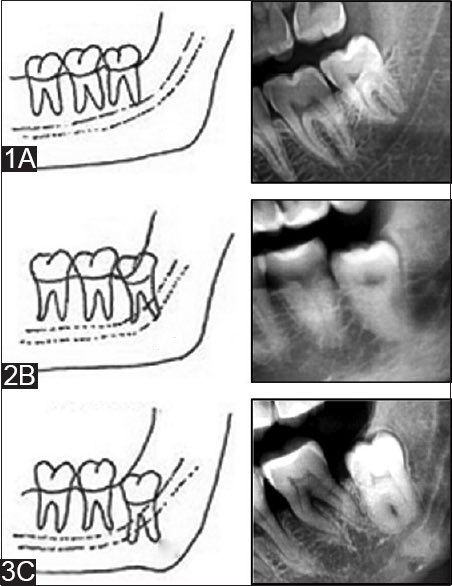

صعوبة خلعه؟ الصعوبه تعتمد على بزوغ الضرس:

١-ظاهر بشكل كامل وهو الأسهل

٢- يظهر بشكل جزئي

٣- مدفون بالكامل وهو الأصعب في الغالب